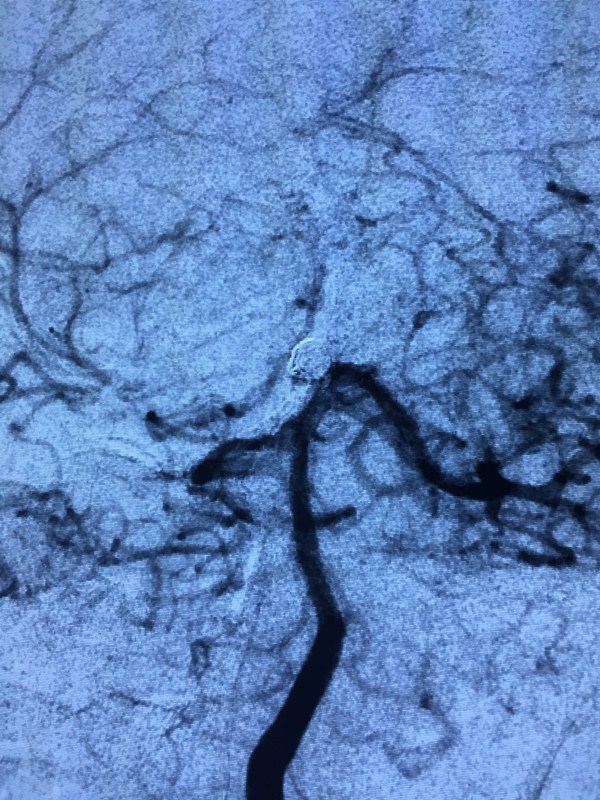

术前3D造影

术后动脉瘤栓塞情况